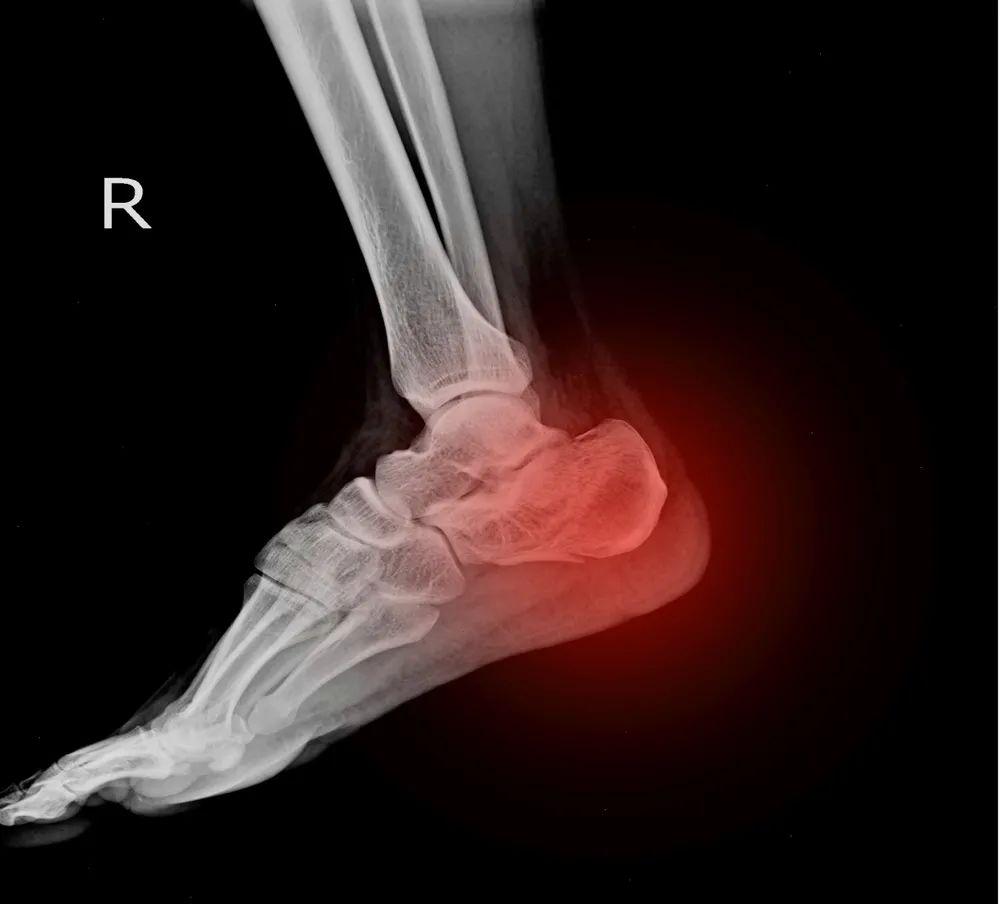

5、 跟骨应力性骨折

跟骨骨折中有一部分为应力性骨折,易发生在跟骨距下关节后下部,表现为活动增加和地面变硬时明显,休息时疼痛不缓解。